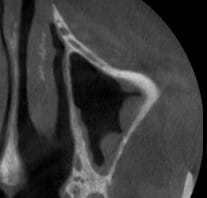

en voilà un autre; question:

comment gérer la découpe du volet osseux avec une artère volumineuse intra-osseuse sans provoquer d'hémorragie ?

ci joints quelques clichés.

T'as une pano, car les coupes dont pas super explicite

ci-joint la coupe panoramique

j'ai juste un servotome

j'ai l'impression que l'idéal serait encore de dessiner une

fenêtre n’atteignant pas l'artère mais pas sûr de pouvoir

passer les curettes